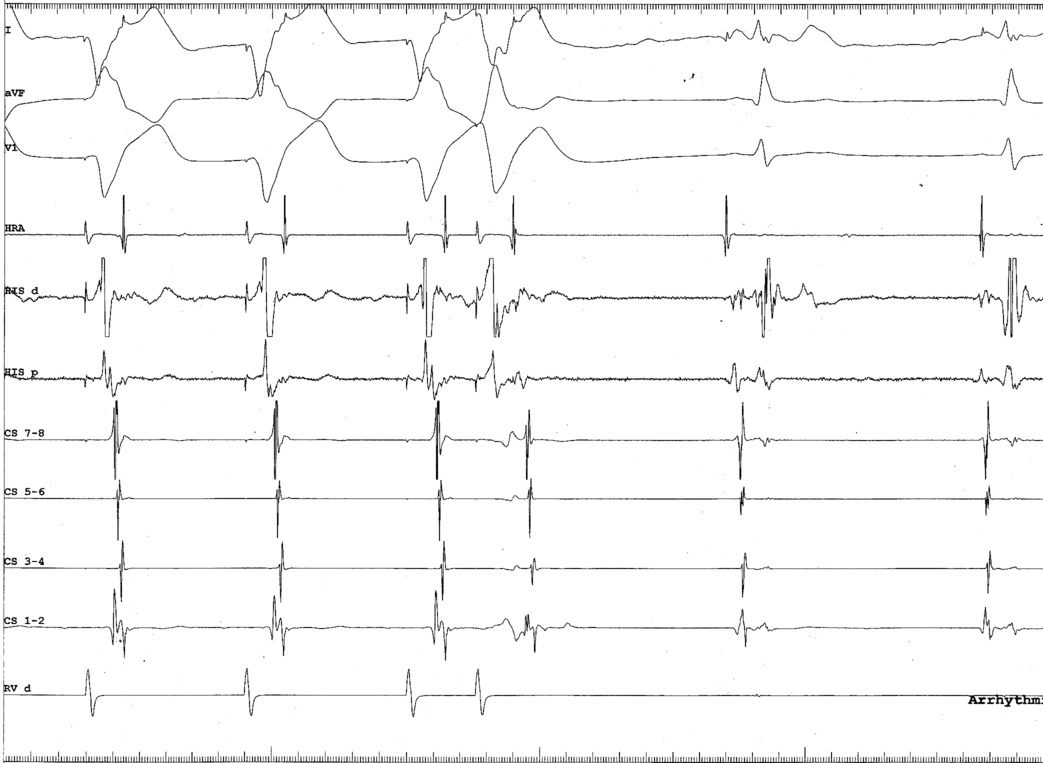

#7 Be afraid of ablating septal APs with A / V pacing

asap_ablation_tachy.jpg